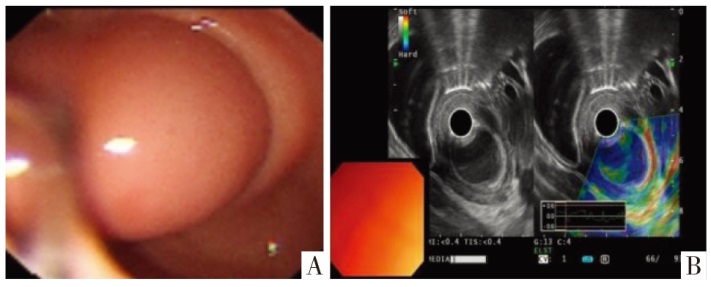

超声内镜影像。A图为内镜下影像,B图为超声影像。可见胃窦隆起性病变,起源于黏膜下层。